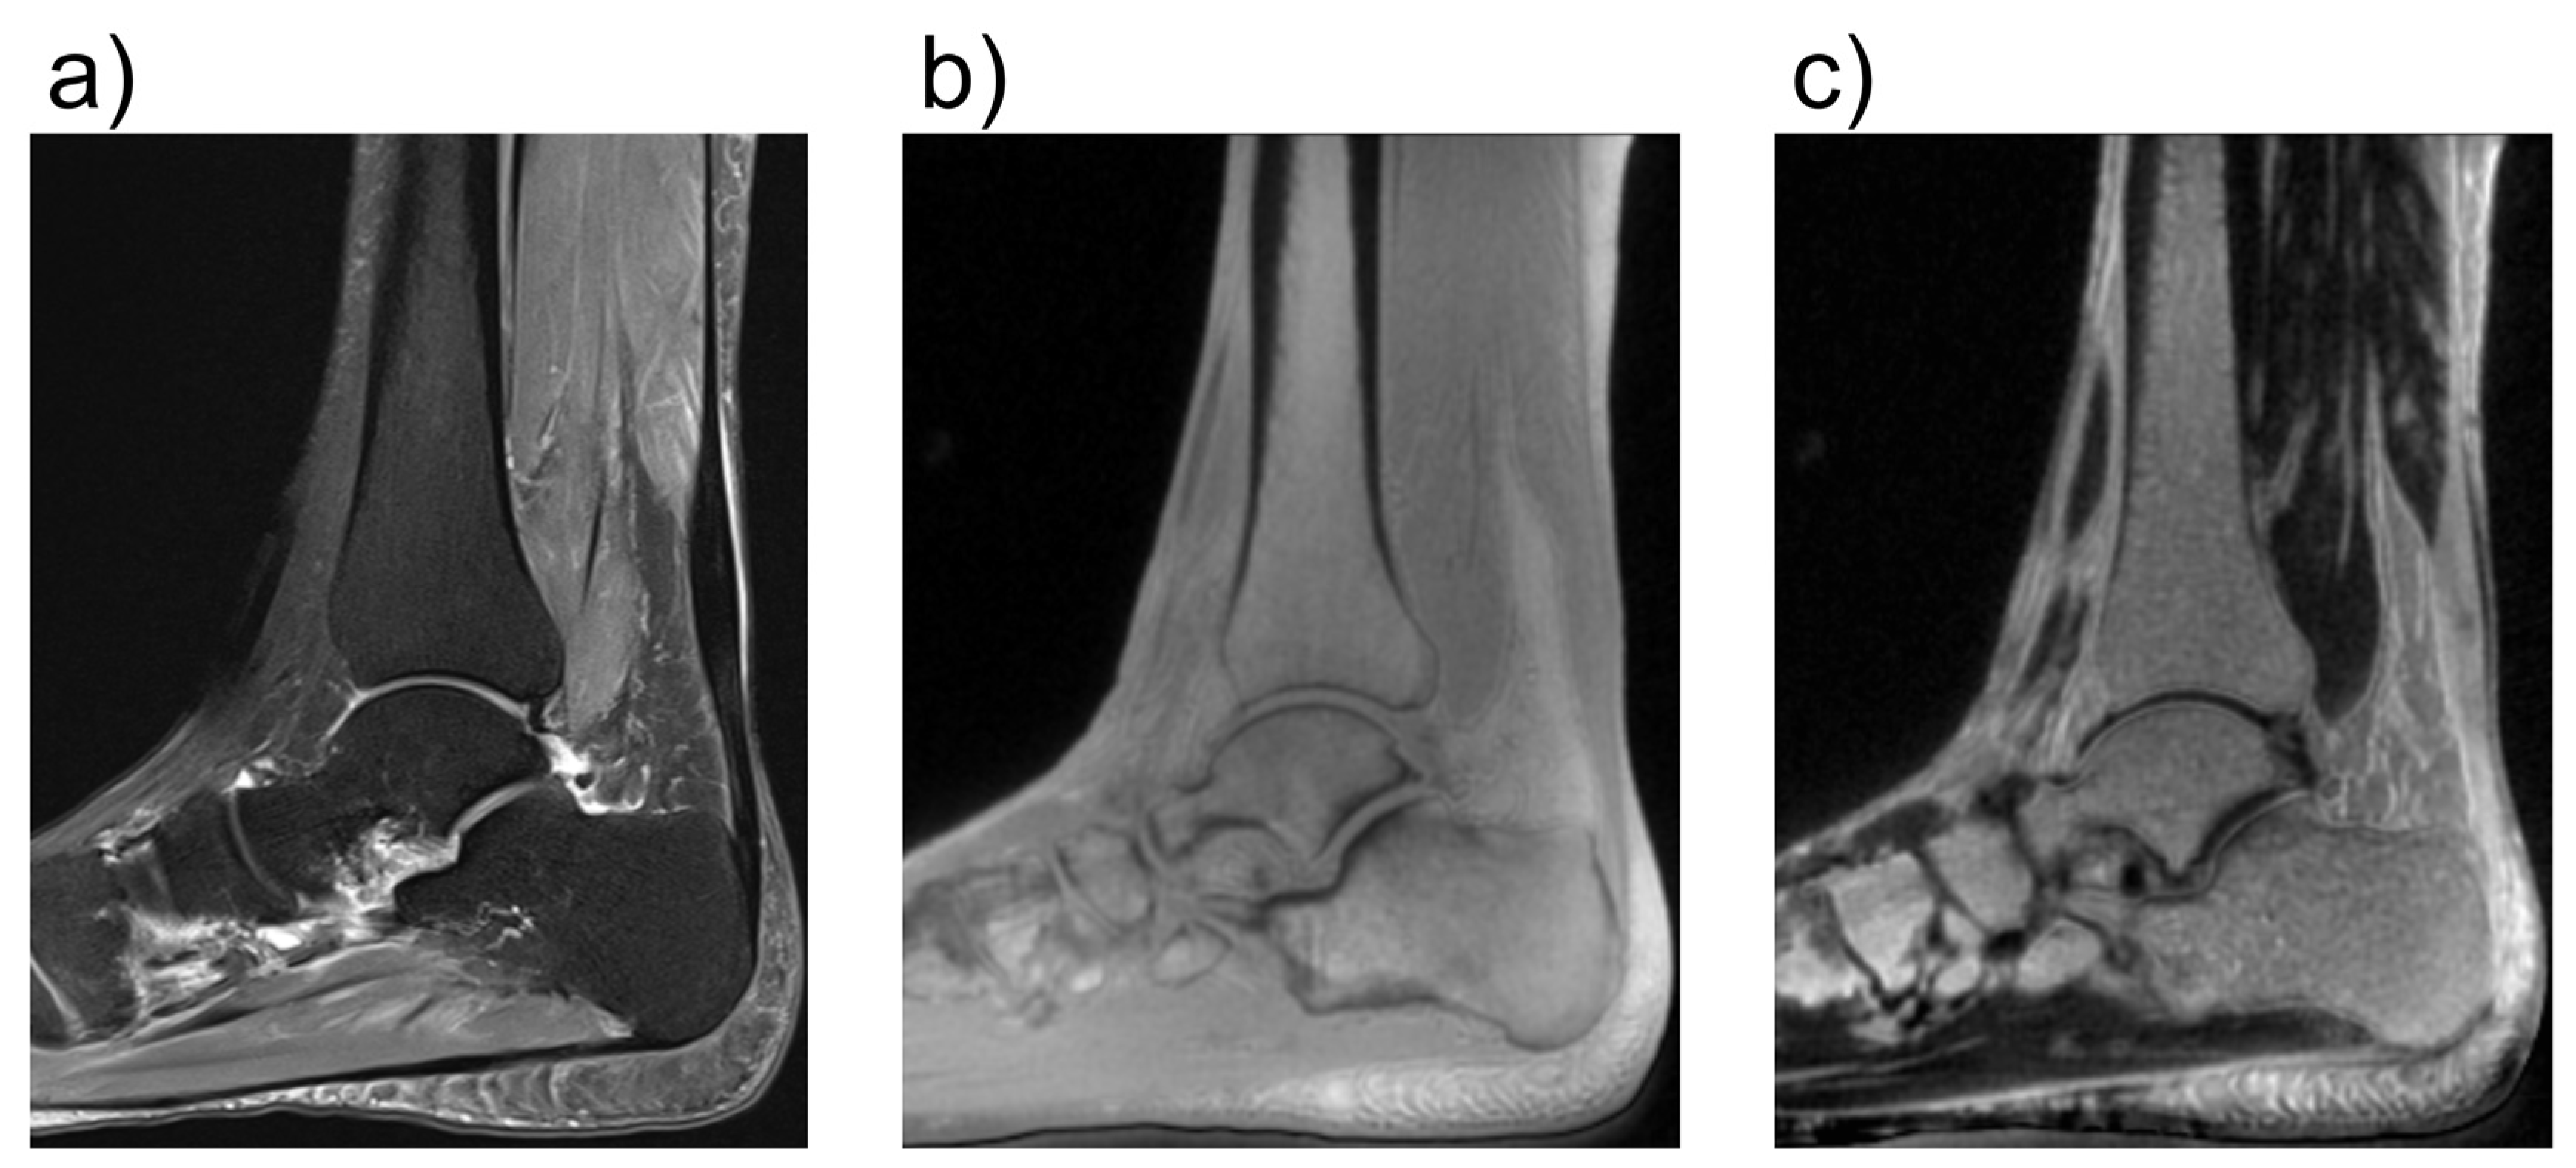

2.1. Conventional MRI

- Fritz, B.; Bensler, S.; Thawait, G.K.; Raithel, E.; Stern, S.E.; Fritz, J. CAIPIRINHA-accelerated 10-min 3D TSE MRI of the ankle for the diagnosis of painful ankle conditions: Performance evaluation in 70 patients. Eur. Radiol. 2019, 29, 609–619. [Google Scholar] [CrossRef]